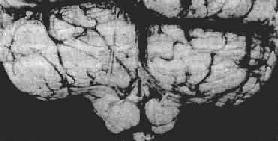

图16-8 小脑扁桃体疝

示小脑切迹,两侧扁桃体疝形成